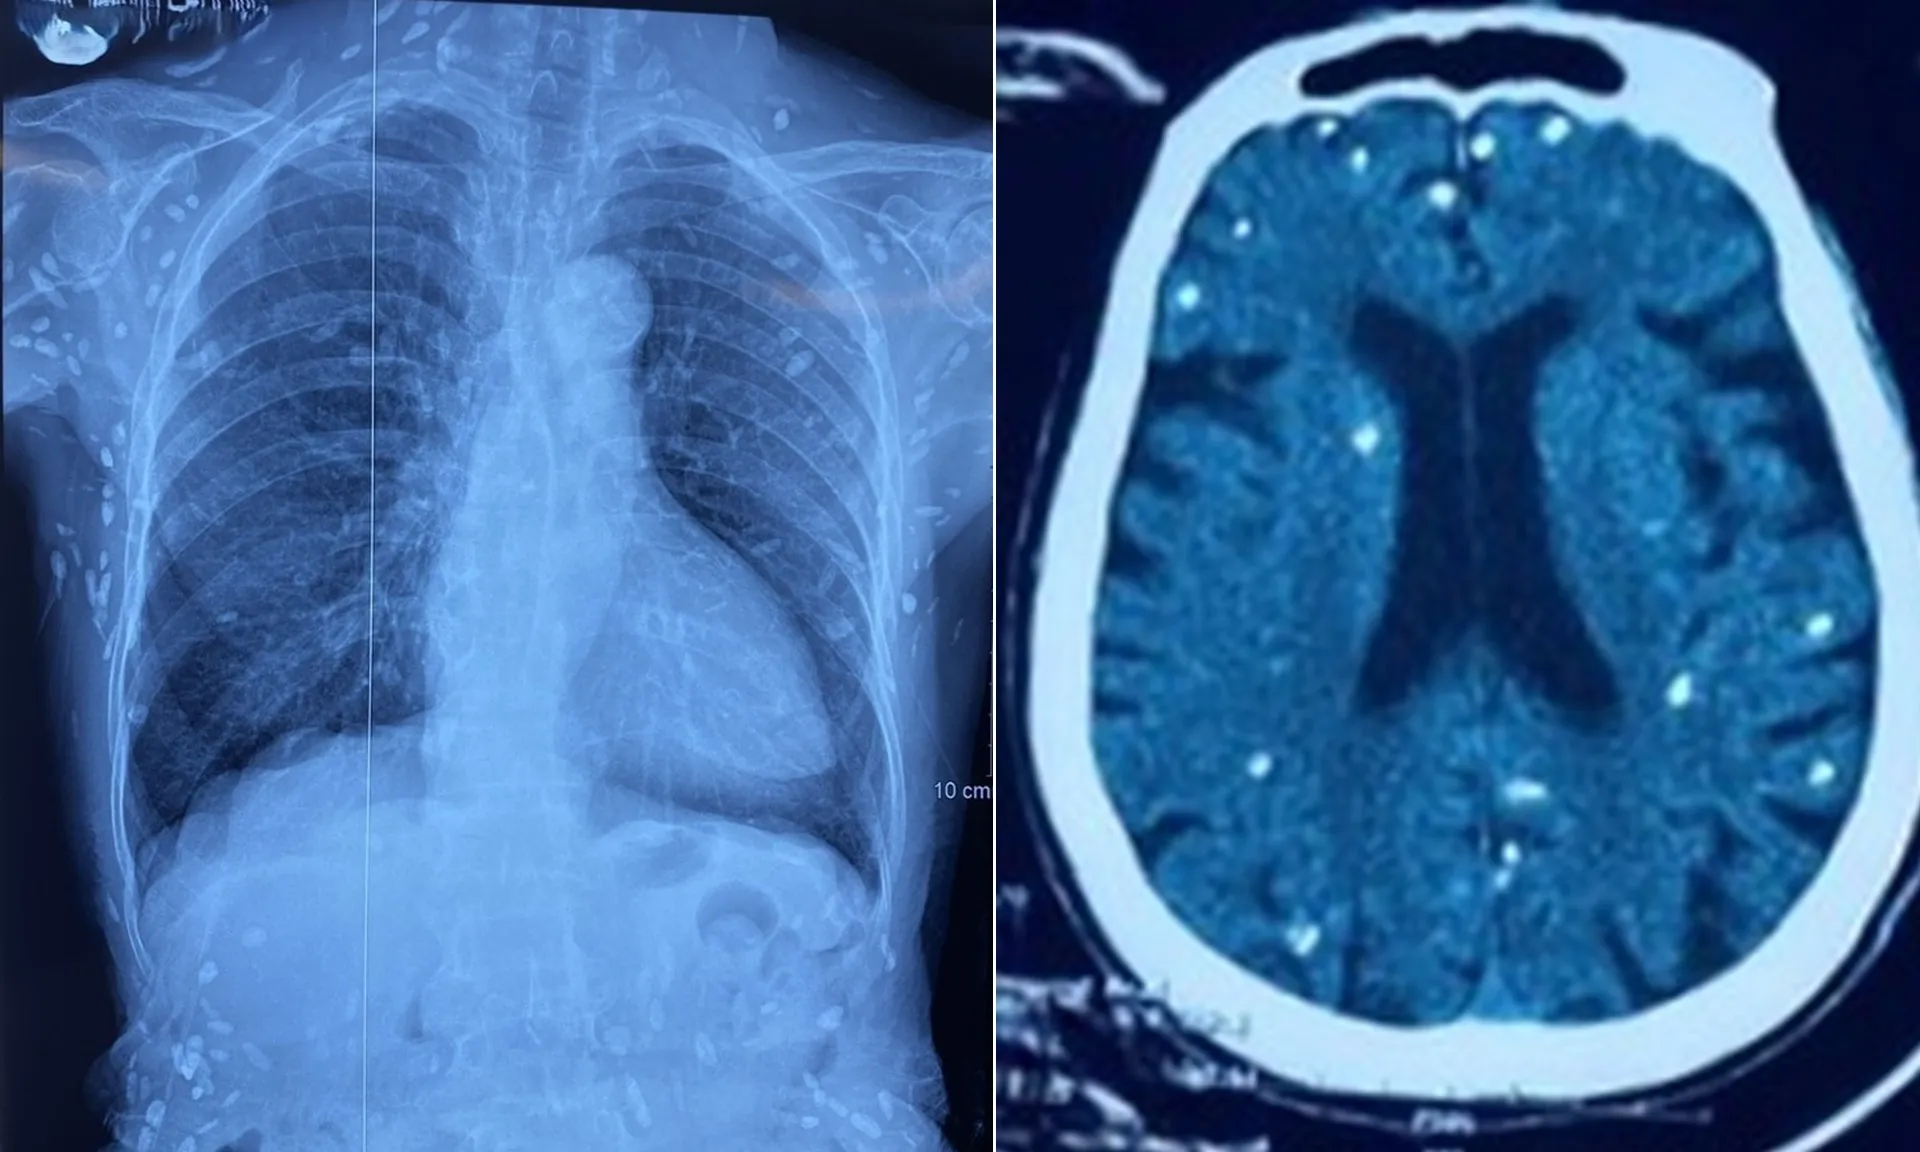

Nữ bệnh nhân (sinh năm 1948) được chuyển lên từ tuyến trước vì rối loạn ý thức đe dọa suy hô hấp, hình ảnh cắt lớp vi tính sọ não và X-quang ngực cho thấy rất nhiều nốt cản quang trong nhu mô não và dưới da vùng ngực-bụng.

Một vài u cục với kích thước tương ứng có thể sờ thấy dưới da vùng ngực và cánh tay của bệnh nhân.

Mặc dù xét nghiệm kháng thể IgM với sán dây heo âm tính, các tổn thương trên X-quang gợi ý bệnh nhân trước đây bị nhiễm ấu trùng sán dây heo, sau đó các nang sán trở nên vôi hóa và tồn tại lâu dài trong tổ chức.

Nang sán dây heo có thể tự thoái hóa hoặc bị vôi hóa, tạo nên nhiều hình ảnh cản quang phát hiện được trên phim X-quang như trường hợp bệnh nhân trên.